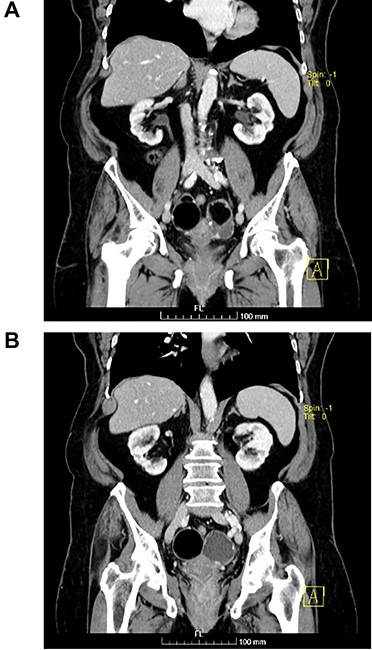

(A and B) Coronal images of CT showing bilateral ovarian lesions.

The authors report the case of an asymptomatic 76-year-old female patient, referred to our Gynaecologic Clinic, due to suspicious adnexal lesions on a pelvic ultrasound (US). Menopause occurred at age 53. She had no history of abnormal uterine haemorrhage. Her menstrual cycles had been regular. She had had three gestations: two late abortions and one normal delivery, after which she breastfed. At our clinic, upon examination, vulva, vagina and cervix had no apparent lesions. The vaginal US revealed a right adnexal avascular cystic lesion of 65 mm, a left adnexal hyperechogenic cystic lesion of 60 mm, a normal sized uterus, a diffusely heterogeneous myometrium, an endometrial thickness of 8 mm and heterogenous intracavitary liquid. Her risk of ovarian malignancy assessment (ROMA) score was 28.1%, for a cut-off of 25.3%. Cancer antigen (CA) 125 and Human epididymis protein 4 (HE4) were 25.9 and 98.2, respectively. Lactate dehydrogenase (LDH), alpha fetoprotein (AFP) and beta human chorionic gonadotropin (bHCG) were normal. She subsequently had a magnetic resonance (MR) done (Fig. 1), which suggested bilateral ovarian teratoma. She also had an upper digestive endoscopy and a hysteroscopy that were normal and a computed tomography (CT) done (Figs 2–4) that showed: in the right adnexal region, a solid well-demarcated tumoural mass of 55 mm, with predominantly fat density, peripherical calcifications and a central hyperdense image (similar to a tooth), suggestive of a teratoma; in the left adnexal region, a predominantly cystic bilobated tumoural mass of 65 mm, with peripherical calcifications and an area of fat density, also suggestive of teratoma; and no additional disease. This case was presented at our Multidisciplinary Tumour Board, where surgery was proposed. Thus, she underwent exploratory laparotomy, peritoneal washing, total hysterectomy and bilateral adnexectomy, which ran uneventfully. Intra-operative frozen section excluded ovarian malignancy. She had an uneventful recovery and was discharged home on the third post-operative day. The pathological report revealed bilateral mature cystic teratoma with representation of the three germinative layers and thyroid parenchymal tissue (struma ovarii) (Fig. 5). Both ovaries were atrophic and had a cavitated lesion covered by respiratory epithelium with hyaline cartilaginous, adipose, smooth muscular and mucosa-associated lymphoid tissues (positivity for CD3 and CD20), seromucinous glands and thyroid follicles (homogenous positivity for thyroglobulin). Thyroid follicles were well differentiated, without features of malignancy. Fallopian tubes were normal. There were also uterine leiomyomas and a mucosal endocervical polyp. She was euthyroid and had a thyroid US done, which was normal. Follow-up at first post-operative month, remaining asymptomatic.